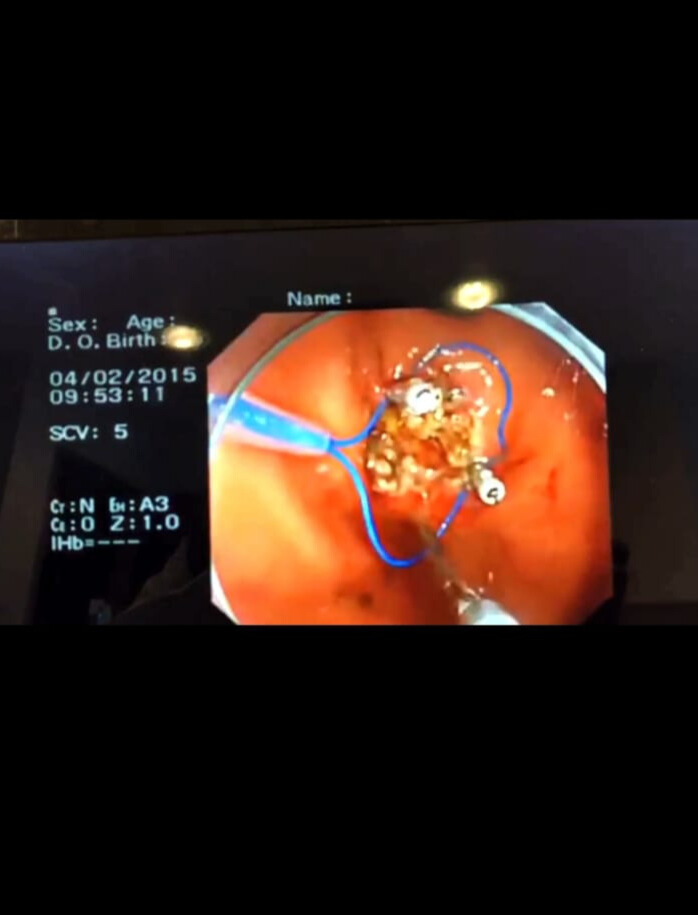

Endoloop, cerrahi prosedürlerde özellikle laparoskopik ameliyatlarda kullanılan bir ligasyon aracıdır. Temel olarak önceden hazırlanmış, emilebilir bir sütür materyalinden oluşan halka şeklinde bir bağdır. Endoloop, damar ya da doku saplarını güvenli bir şekilde bağlamak ve kesmeden önce kanamayı kontrol altına almak amacıyla kullanılır.

Endoloop, cerrahi prosedürlerde özellikle laparoskopik ameliyatlarda kullanılan bir ligasyon aracıdır. Temel olarak önceden hazırlanmış, emilebilir bir sütür materyalinden oluşan halka şeklinde bir bağdır. Endoloop, damar ya da doku saplarını güvenli bir şekilde bağlamak ve kesmeden önce kanamayı kontrol altına almak amacıyla kullanılır. Uygulama sırasında halka hedef dokuya geçirilir, ardından çekilerek sıkıştırılır ve ligasyon tamamlanır. Özellikle apendektomi, kolesistektomi gibi minimal invaziv cerrahilerde pratik, hızlı ve güvenilir bir çözüm sunduğu için tercih edilmektedir. Polip veya doku ligasyonu için tasarlanmış endoloop sistemidir. Tek kullanımlık ve steril paketlidir.

Polip rezeksiyonu sonrası kanama kontrolü veya mukozal dokuların bağlanmasında kullanılır.